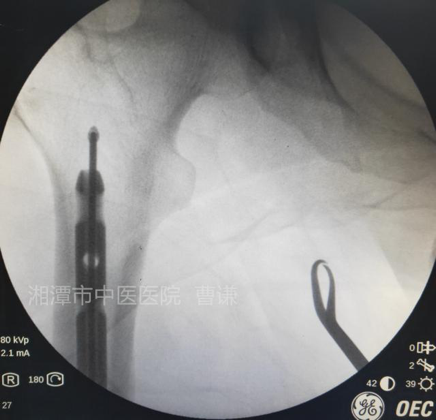

通过正侧位透视进钉点位置,正位位于髁间窝中点稍偏外侧,侧位位于Blumensaat线稍前方。避免损伤后交叉韧带及髓内钉穿出后侧皮质。

扩髓后沿导针置入髓内钉,注意尾端不要突出髁间窝,髓内钉尖端应置于小转子水平。

安装瞄准器后分别置入远端锁钉及近端锁钉,透视锁定良好。